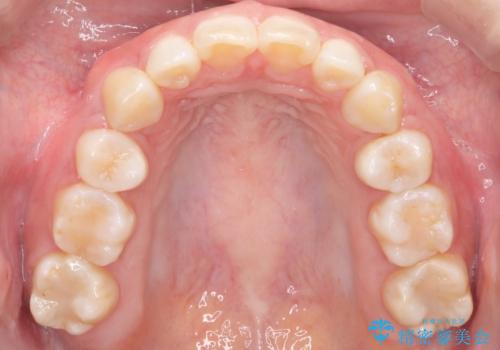

治療について

抜歯をすることでしっかり前歯を後方に移動させて、引っ込めることができました。